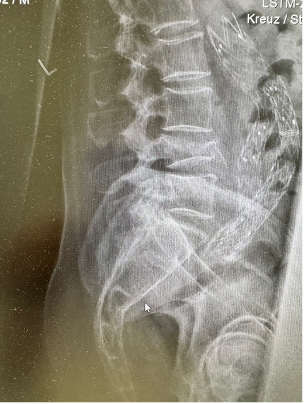

Patient fell from ladder and developed lumbar L4 fracture, he was addressed in minimal invasive technique with L4 replacement and stabilisation. He was able to ambulate without any aids on day 1 after surgery